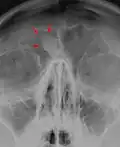

Osteoma of the frontal sinus seen on x-ray -

Osteoma of the frontal sinus on CT -